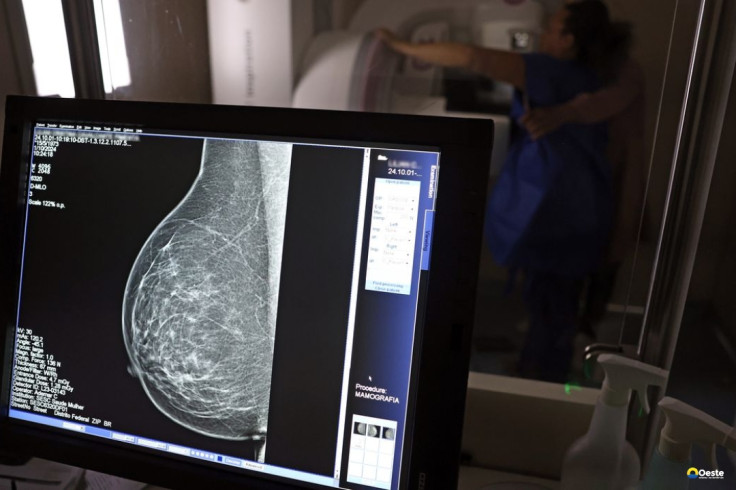

Outubro Rosa: como receber o auxílio-doença em tratamento de câncer

A vice-presidente da Comissão de Previdência Social Pública da Ordem dos Advogados do Brasil do Rio de Janeiro (OAB-RJ), Danielle Guimarães, destaca que o câncer de mama é uma das doenças que mais afetam mulheres no Brasil, impactando não apenas a saúde física e emocional, mas também a capacidade de trabalho e a segurança financeira das pacientes.

Segundo Danielle, o auxílio por incapacidade temporária, conhecido como auxílio-doença, destina-se a seguradas que ficam temporariamente incapacitadas para exercer suas atividades profissionais devido ao câncer de mama ou aos efeitos do tratamento (cirurgias, quimioterapia, radioterapia e seus efeitos físicos e emocionais).